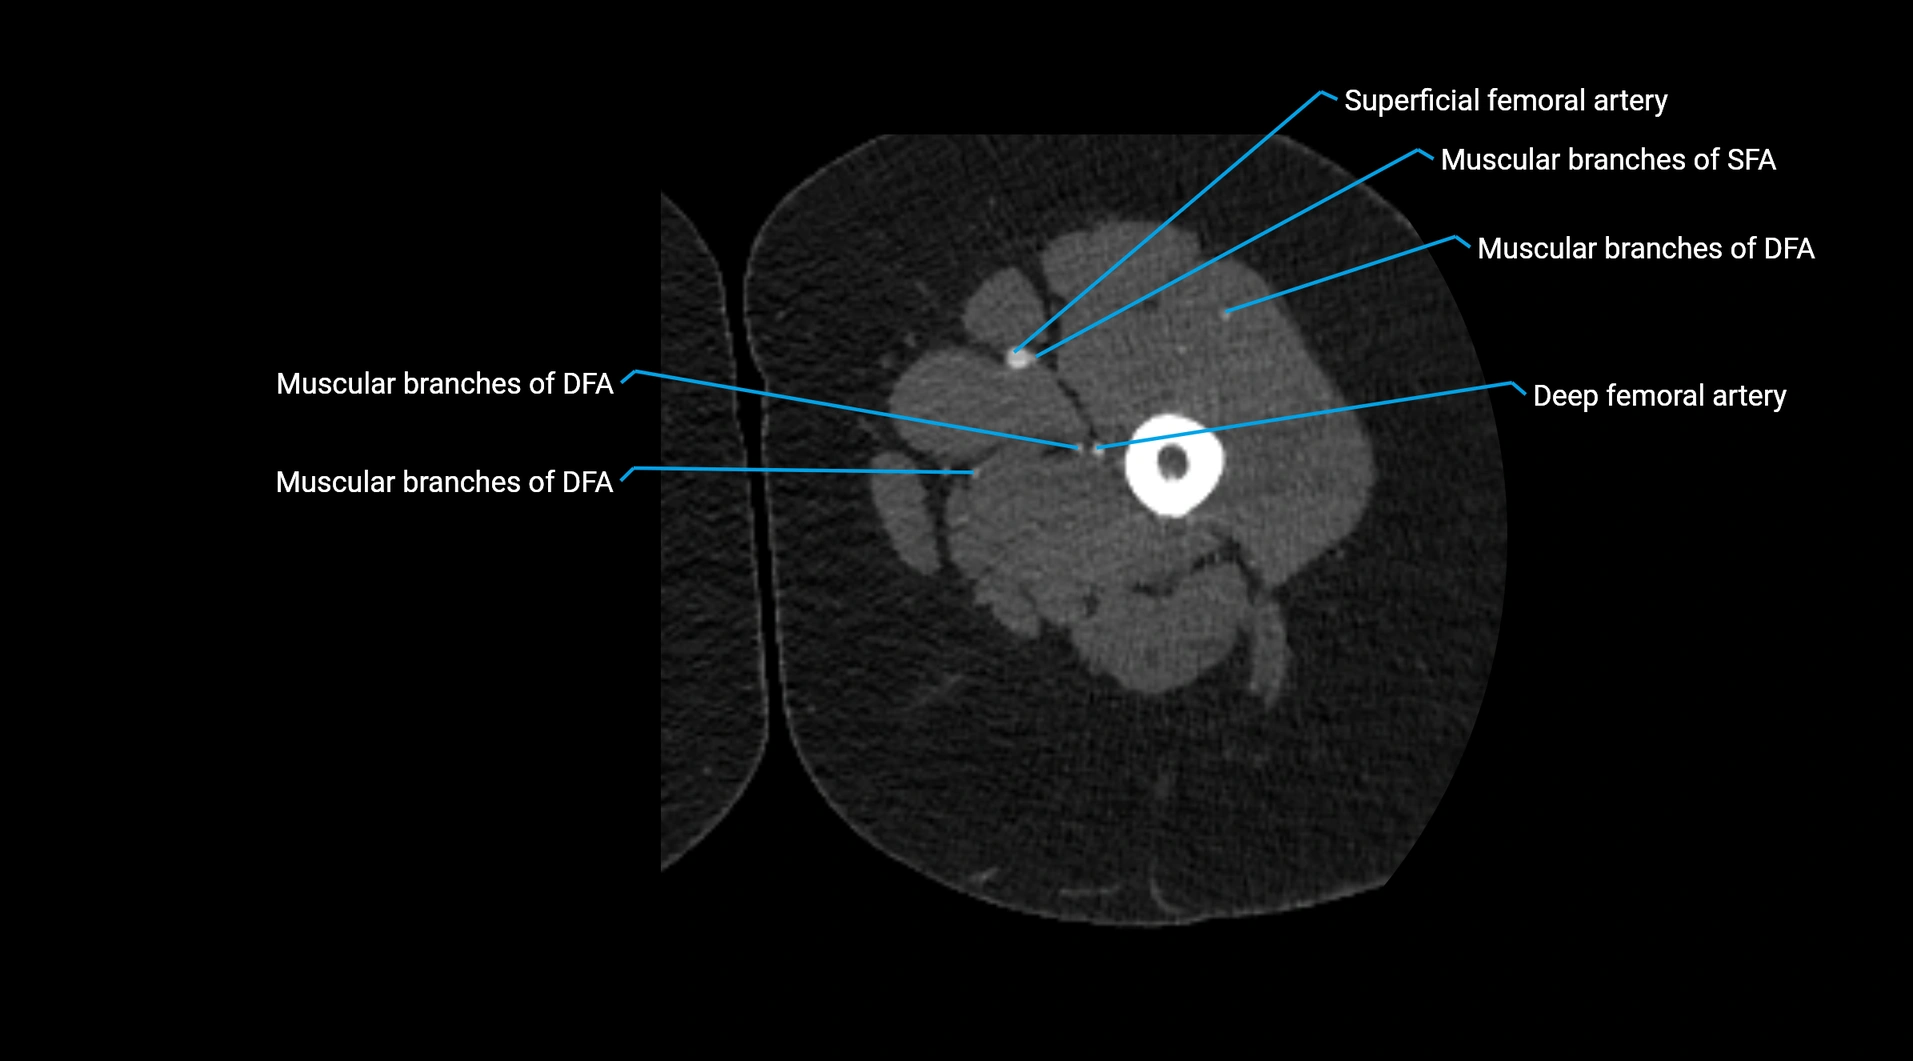

Contrast-enhanced CT (CTA):

• Gold standard for abdominal aortic imaging

• Provides excellent detail of lumen, wall, aneurysm, thrombus, and branch vessels

• Multiplanar and 3D reconstructions help in aneurysm measurement, stent graft planning, and dissection evaluation